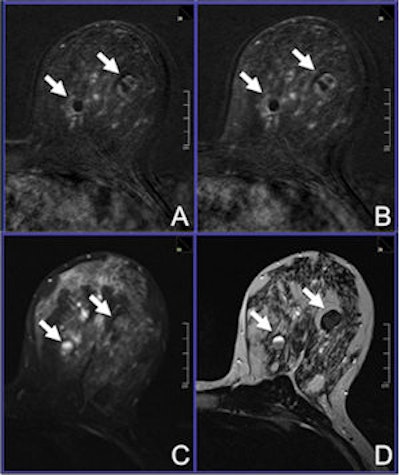

A 42-year-old woman was referred to MRI due to dense breast tissue and multiple cystic lesions, several of them showing inhomogeneous echogeneity and dorsal acoustic shadowing, classified as BI-RADS 0. A: Early contrast-enhanced T1-weighted subtraction. B: Delayed contrast-enhanced T1-subtraction. C: Short tau inversion-recovery image. D: T2-weighted, turbo spin-echo image reveals the lesions to be proteinaceous cysts (arrows). Image courtesy of Dr. Claudio Spick.